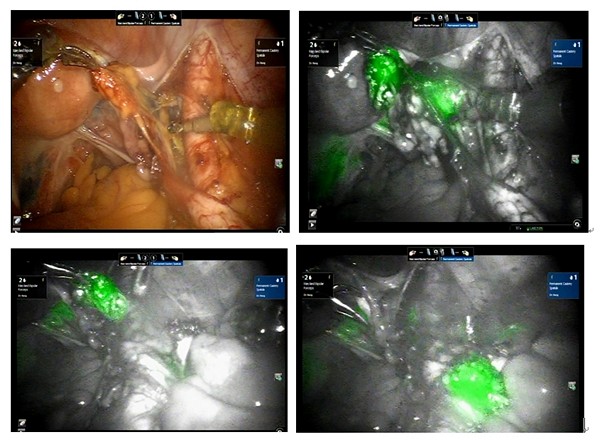

圖說:達文西螢光系統導引下可以精準地切除所有可疑淋巴結,提高正確的診斷及癌症分期。

雖然台灣腹腔鏡技術已經很先進,但面對難度較高的手術或肥胖患者等特定狀況時,達文西機械手臂的表現往往更優越。龐醫師表示,達文西手術可以讓醫師不用長時間站著開刀,較專心於手術中,手術病人更安全外,在達文西手術系統中特有的螢光系統導引下,能讓醫師把可疑的前哨站骨盆淋巴結看得一清二楚,協助醫師精準地清除骨盆與主動脈的轉移淋巴結,降低病患出血量,讓後續治療順利進行,大幅降低病患手術風險。